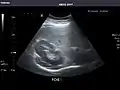

Right kidney